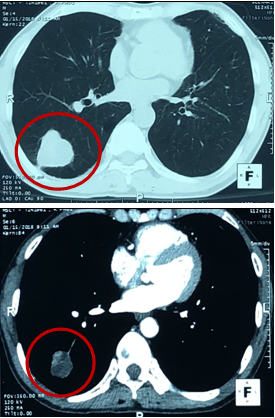

-   Cắt lớp vi tính lồng ngực: U thùy dưới phổi phải kích thước 56x81mm, ngấm thuốc sau tiêm. Khối mờ đỉnh phổi trái kích thước 28mm, nốt mờ nhỏ phân thùy lưỡi phổi trái.

Hình 1: Hình ảnh chụp cắt lớp vi tình lồng ngực

-   Chụp cắt lớp vi tính lồng ngực:

Trước điều trị: U phổi phải kích thước 56x81mm

Sau điều trị: U phổi phải kích thước 35x40mm

Trước điều trị: Khối mờ đỉnh phổi trái kích thước 28mm, nốt mờ thùy dưới phổi trái.

Sau điều trị: Khối mờ đỉnh phổi trái là dải xơ hóa, nốt mờ nhỏ thùy dưới phổi trái không còn.